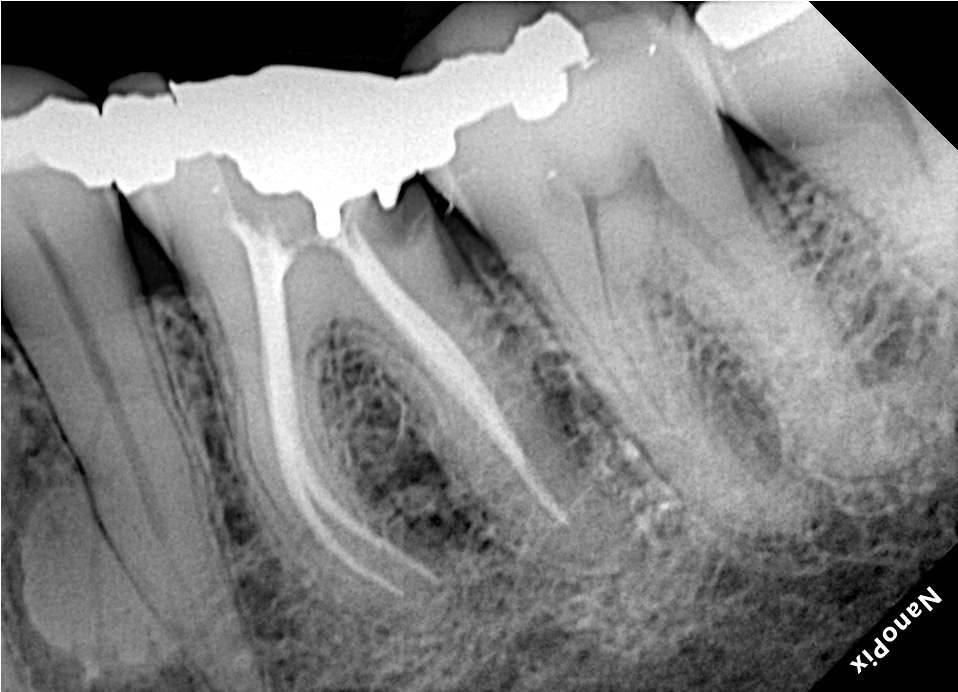

Raio X portátil e sistema de captura de imagem

Os aparelhos de raio X portáteis possibilitam ergonomia e praticidade na execução de radiografias intrabucais. Associadas ao sensor digital possibilitam menor tempo de exposição ao paciente e profissional.